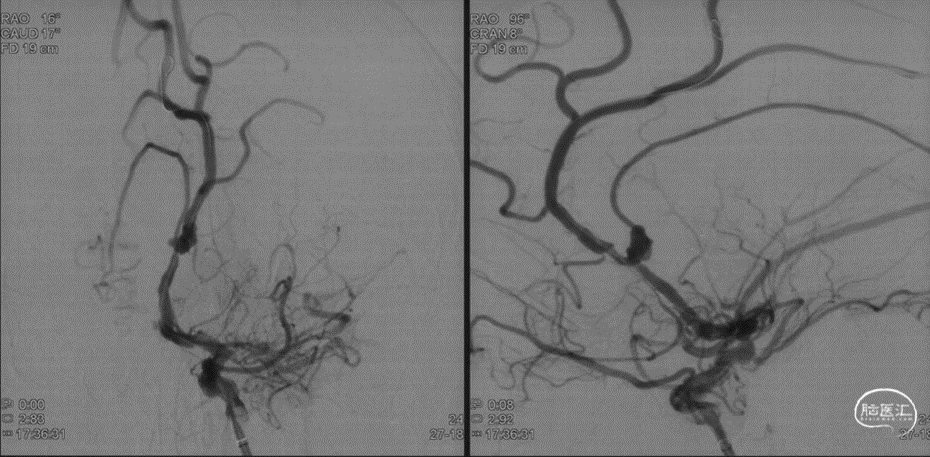

本例患者是左侧大脑前动脉A2段动脉瘤,形态不规则,合并载瘤动脉狭窄,采用血流导向装置植入治疗后获得较好的影像学结果。